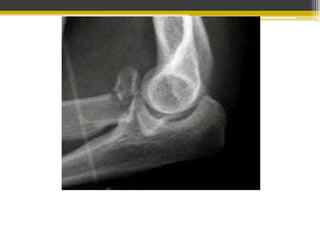

Fracturas distales del húmero

• Afectan a las metáfisis pueden o no extenderse a

la superficie articular.

Fracturas intraarticulares

 Columna simple: Cóndilo medial y

lateral

 Dos columnas: Intercondíliea en T y Y

Fracturas extraarticulares

• Extracapsular: Supracondílea y la epicondílea

medial y lateral

• flexión: desplazamiento anterior del extremo

distal y de la art. Del codo

• Extensión: Desplazamiento posterior de la

parte distal del húmero.

• Intracapsular: transcondílea.

Fractura de epitróclea

Fractura supracondílea

• Radiología: Proyección lateral del codo

inclinado y desviado hacia atrás.